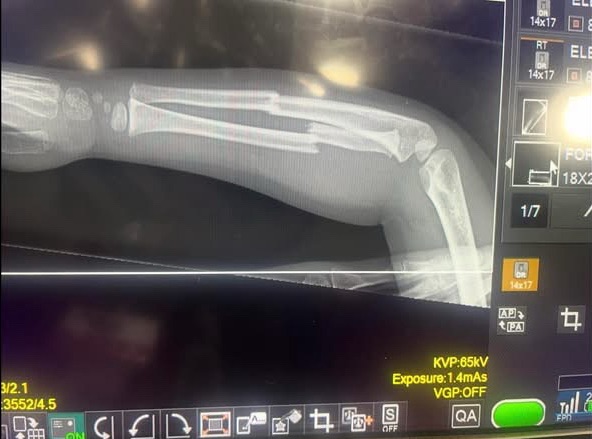

Her daughter’s arm was broken. In two places. And according to the doctor, it was not an accident. The breaks were consistent with the arm being stepped on or slammed in a door.

A child’s arm was broken. Twice. In one day.